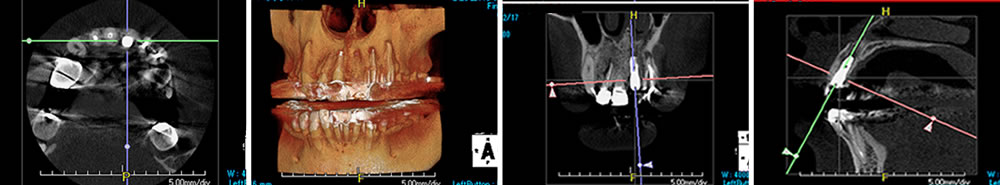

【CT画像(術前)2016年9月10日】

口腔内の状態を把握し、適切なインプラント手術を実施するため、デンタルエックス線写真、パノラマエックス線写真、CT撮影、歯周病検査、唾液検査を実施しました。

初期治療終了後に、欠損部の治療としてブリッジとインプラント補綴治療の利点、欠点、治療期間、費用、手術方法、合併症などを十分に説明したところ、患者さまはインプラントを用いた補綴治療を希望されました。インプラントの方法については抜歯即時、待時のどちらを選択するか考えてもらい、1回の手術と骨欠損を最小限に抑えるために「抜歯即時埋入」で手術を行うことになりました。

2016年12月にインプラント手術を実施。まずは、インプラントを埋入する部分の左上顎の1番の歯に浸潤麻酔を行い、抜歯しました。その後、抜歯した部分にインプラント体(1番目:半径3.75mm×10mm スプラインHAインプラント zimmer社)を通法に従い埋入し、ヒーリングキャップを締結しました。